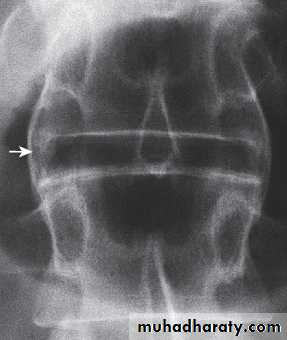

In established AS, radiographs of the sacroiliac joint show irregularity and loss of cortical margins, widening of the joint space and subsequently sclerosis, joint space narrowing and fusion.Lateral thoracolumbar spine Xrays may show anterior ‘squaring’ of vertebrae due to erosion and sclerosis of the anterior corners and periostitis of the waist.

Bridging syndesmophytes may also be seen. These are areas of calcification that follow the outermost fibres of the annulus

Investigations

In advanced disease, ossification of the anterior longitudinal ligament and facet joint fusion may also be visible. The combination of these features may result in the typical ‘bamboo’ spine.Erosive changes may be seen in the symphysis pubis, the ischial tuberosities and peripheral joints.